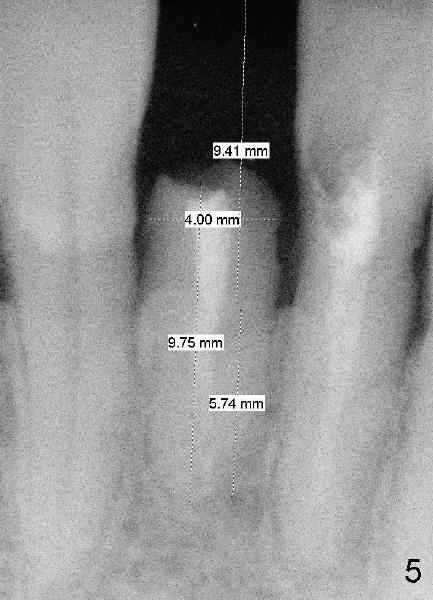

Fig.5 shows unfavorable crown/root ratio (9.41 mm vs. 5.74 mm); Fig.6 shows the longest post space that can be obtained using #2 Peeso bur. Return to main article